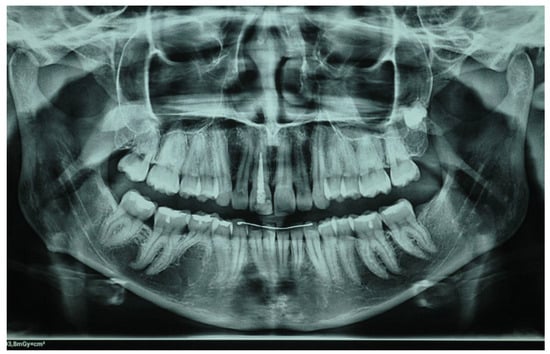

2. Clinical Case